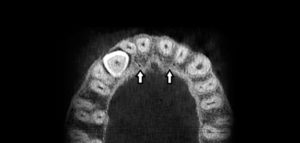

158 – Uso intraoperatorio de la CBCT para la identificación y localización de canales calcificados

Se sabe que la tomografía computarizada de haz cónico (CBCT) produce exploraciones tridimensionales de la dentición, las estructuras duras maxilofaciales y la relación de las